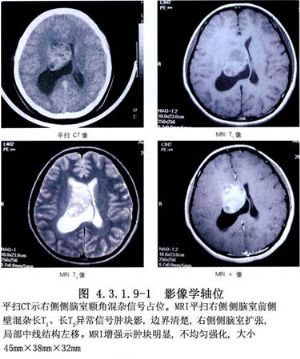

側腦室內腫瘤的發生率較低,據國內外文獻報道約佔顱內腫瘤總數的0.75%~2.8%。在側腦室前部和體部者,多爲室管膜瘤,在三角部、顳角和枕角區者,多爲乳頭狀瘤或腦膜瘤。側腦室周圍、丘腦和腦室室管膜下生長的膠質瘤,也可長入腦室內。其他如上皮樣囊腫或皮樣囊腫等也偶可見到。側腦室內腦膜瘤約佔顱內腦膜瘤的2.5%~6.3%,以女性較多,年齡多在30歲左右,且好發於左側側腦室。室管膜瘤則以嬰幼兒和學齡前兒童多見(圖4.3.1.9-1~4.3.1.9-6)。

頸動脈造影顯示脈絡膜前動脈增粗,椎動脈造影顯示脈絡膜後動脈增粗、走行異常和腫瘤染色等,都是確診側腦室腫瘤的有力依據。自CT、MRI問世以來,確診已較簡易、安全。由於手術經驗的積累,療效亦不斷提高,大多能全切治癒。